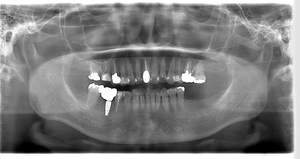

インプラント治療の症例4

レントゲン写真

- Befor

- After

口腔内写真

| 年齢 | 50代・男性 |

|---|---|

| 主訴 | 部位:左下6番7番 主訴:左下奥歯腫れて痛い。 |

| 治療内容 | 左下6番抜歯、左下6番7番骨造成、インプラント埋入 |

| 治療費 | 合計:1,232,000円 ・内訳 診断料:55,000円 サージカルガイド2本:66,000円 GBR:110,000円×2本 埋入料:165,000円×2本 静脈内鎮静麻酔:77,000円 2次OPE:22,000円×2本 仮歯:55,000円×2本 上部構造(フルジルコニア):165,000円×2本 (2023年1月現在) |

| 治療期間 | 約8ヶ月 |

| 治療方針 | 元々支台歯に負荷がかかりやすいとされている延長ブリッジを抜歯し、1本単体でしっかりかめるようにインプラントを2本埋入した。骨吸収も進んでいたため、※GBR法で骨造成を同時に行った。 治療と並行して、全顎的な歯周病治療も行い、今後は歯周病が進行しないよう、こまめにメンテナンスに通っていただく。 |

| 特記事項 | ※1 GBR・・・骨再生誘導法。骨の高さや厚みを人工骨や人工膜などを使用し再生する方法 |

| 担当者所見 | 6番は歯根分割された被せ物が7番の欠損部との延長ブリッジとされており、強い咬合と歯周病も相まって負荷がかかり動揺し、歯として機能しなくなったため、抜歯となった。 |